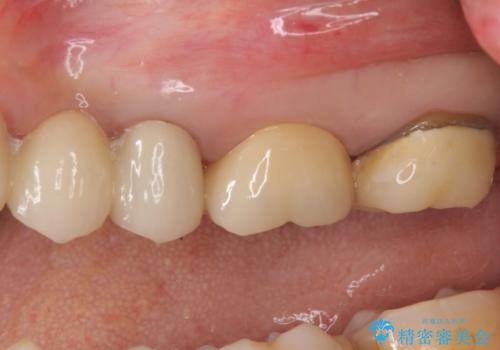

向かい合わせの歯の咬みこみが強くインレーよりも強度の高いクラウンでの治療となりました。その中でも色が白くある程度の薄さでも耐久性を発揮するフルジルコニアクラウンでの修復を行いました。適合も良く色調もとてもなじんだため大変喜んでいただけました。